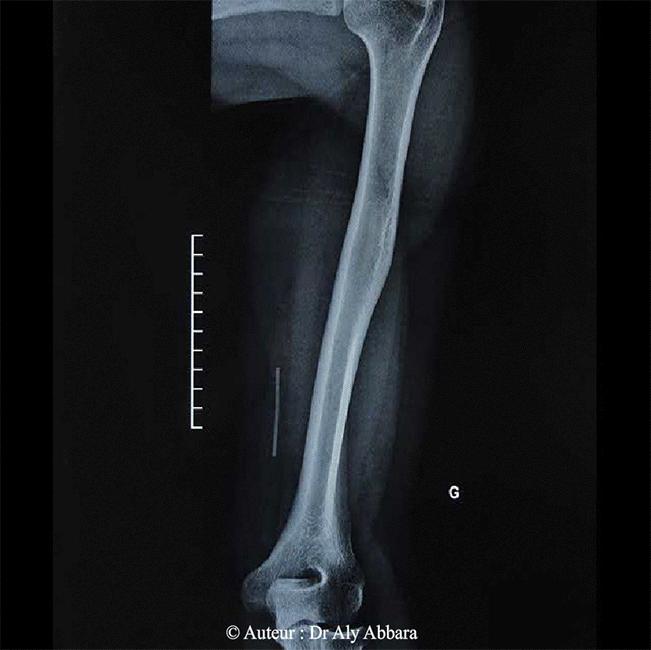

Images montrant un implant contraceptif progestatif migrant profondément dans le tissu sous cutané de la face interne du bras gauche ; il est identifiable sur cette image du fait de sa radio-opacité ; il parait d'être en contact avec la surface extérieure du plan musculaire.

Cliniquement cet implant est impalpable au niveau du site de son implantation (un an après son insertion) et chirurgicalement, il a été retrouvé près du plan musculaire comme le montre cette image radiologique.